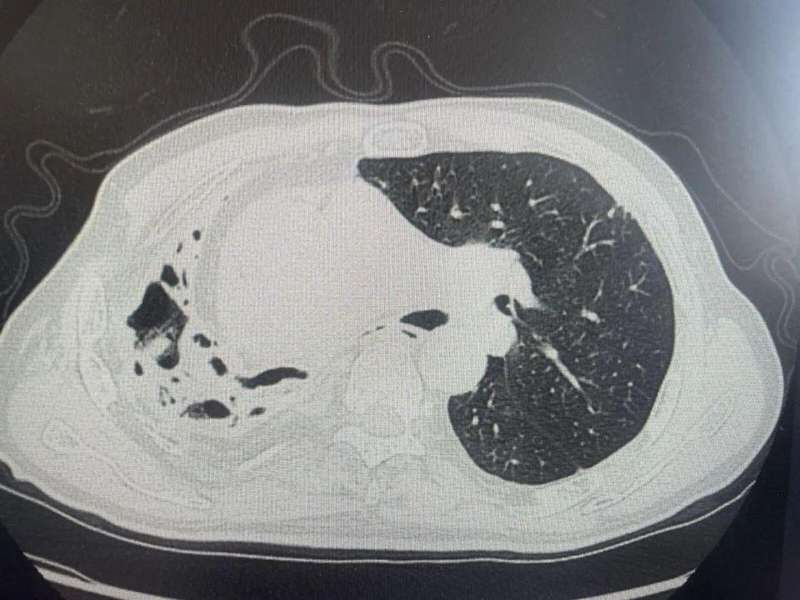

一位七旬老人近期频繁参与春季山林活动,之后出现反复咯血症状。家人起初以为是旧疾复发,但经过详细检查发现,情况远比想象中复杂。他的右肺已呈现明显异常改变,功能受到显著影响。这提醒大家,春季户外活动虽有益身心,却不可忽视环境中的隐形因素。

专家指出,这种真菌的主要天然宿主是竹鼠,在竹林的土壤、腐烂植物残渣中较为常见。人体吸入孢子后,孢子可能在肺部定植并繁殖,引发炎症反应。对于有肺部基础疾病的个体,风险会进一步增加。影像学检查往往显示肺组织结构改变,如蜂窝样外观,肺功能也可能逐步下降。及早发现并进行规范治疗,能帮助病情趋于稳定,后续需定期监测恢复情况。